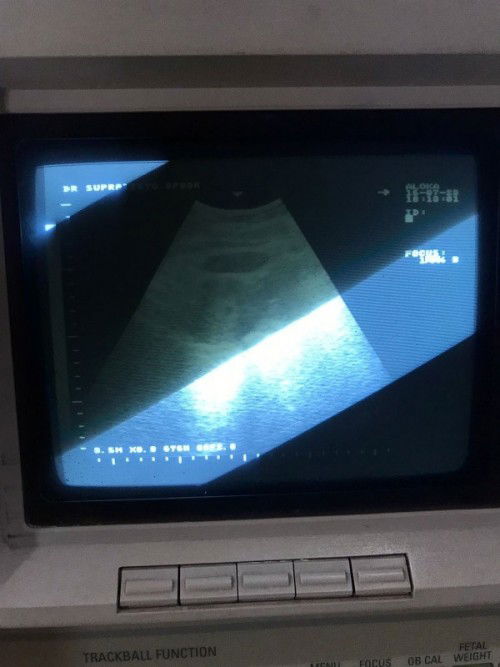

Bunda bunda mau tanya hasil USG

Ini hasil USG aku 6week aku mau tanya ke bunda bunda kantung janin itu yang atass itu atau yang di dalam ada titik kecil itu Bun #seriusnanya #ingintahu #pleasehelp